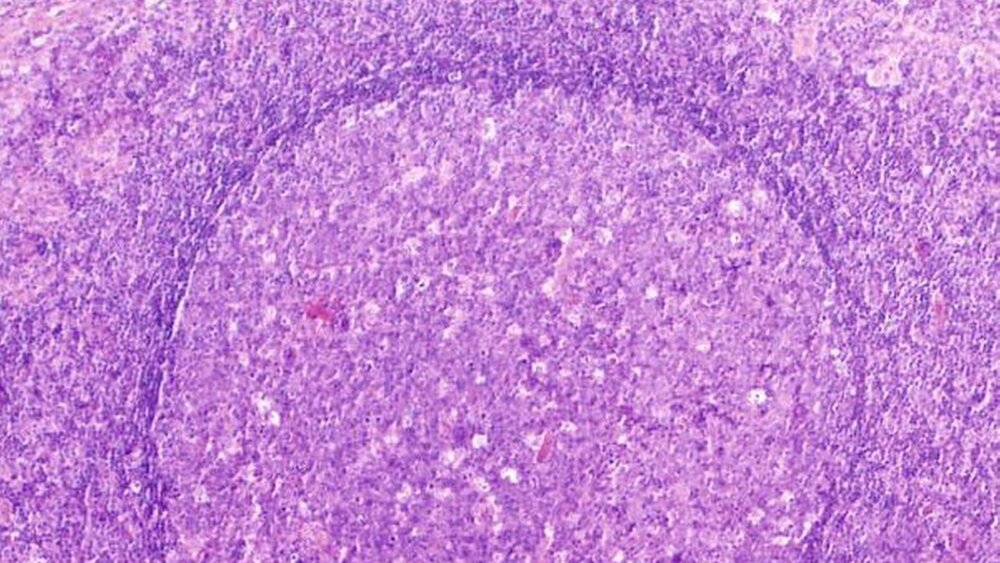

Die histopathologische Beurteilung bestätigte die Verdachtsdiagnose mit diffus großzelligem B-Non-Hodgkin-Lymphom (Abbildung 4a). Immunhistochemisch war der Tumor CD-20- (Abbildung 4b) und bcl-2- positiv. Die Histologie des Lymphknotens zeigte eine weitgehend erhaltene Lymphknotenarchitektur (Abbildung 4c). Die normalerweise bcl-2-negativen Keimzentren zeigten in der durchgeführten Immunhistologie eine kräftige Anfärbung gegen bcl-2 und bewiesen somit auch hier eine Infiltration des Lymphoms.